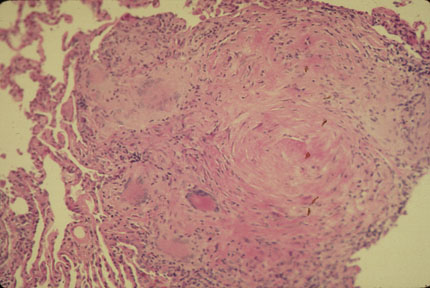

- The histologic hallmark is lymphangitic distribution of non-caseating

granulomas with Langhans' or foreign body type giant cells

- Within the granulomas there may be calcified, rounded, laminated

concretions known as Schumann's bodies

- With the giant cells there are often star-shaped inclusions (Asteroid

bodies)

- The above 2 are characteristic, but not diagnostic, of sarcoidosis

- There is varying degree of fibrosis around granulomas and in the

interstitium

- Sarcoidosis is a diagnosis of exclusion